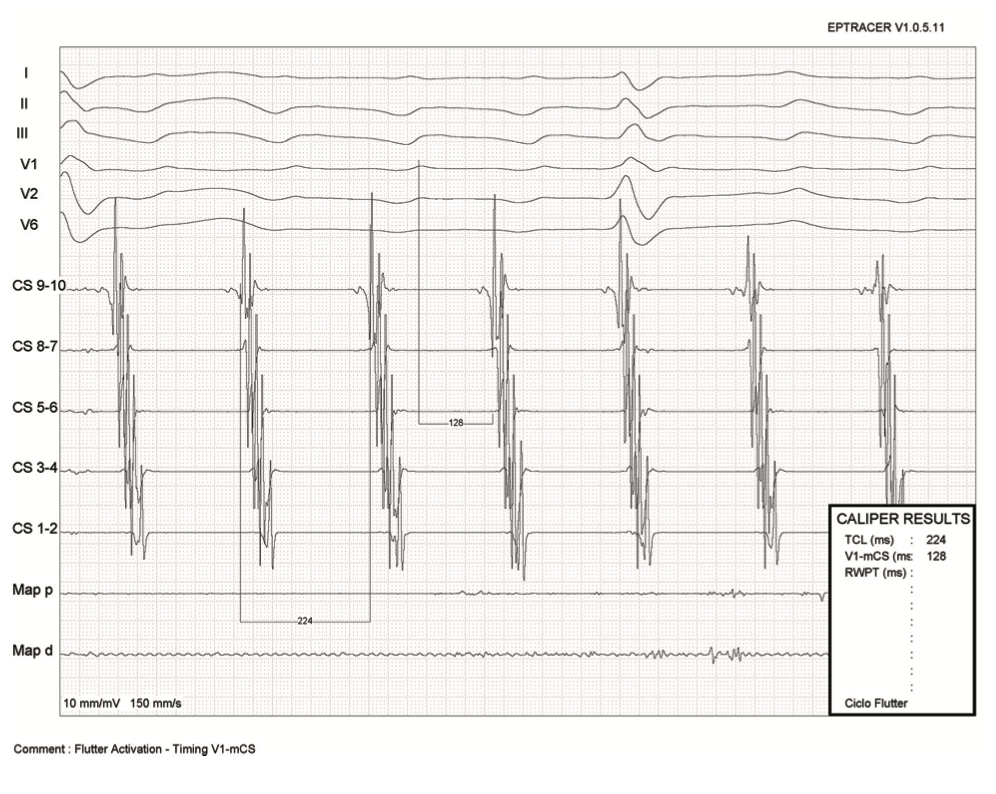

CS atrial activation during AFL was proximal to distal, with a cycle length of 224 milliseconds. The time from the peak of F-wave in lead V1 to the mid CS activation (dipole CS 5-6) was 128 milliseconds (Figure 2), representing approximately 57% of the cycle length, suggesting a peritricuspid circuit.3 The 3D EAM confirmed a counterclockwise-rotating macroreentry (Video 2), and entrainment from the cavotricuspid isthmus (CTI) confirmed a CTI-dependent AFL. CTI ablation guided by ICE and contact force was performed (Video 3), and interrupted the AFL converting to junctional rhythm (Figure 3). Bidirectional block was confirmed by double potentials along the line during proximal CS pacing (Figure 4) in combination with differential pacing of the lateral wall with the ablation catheter.